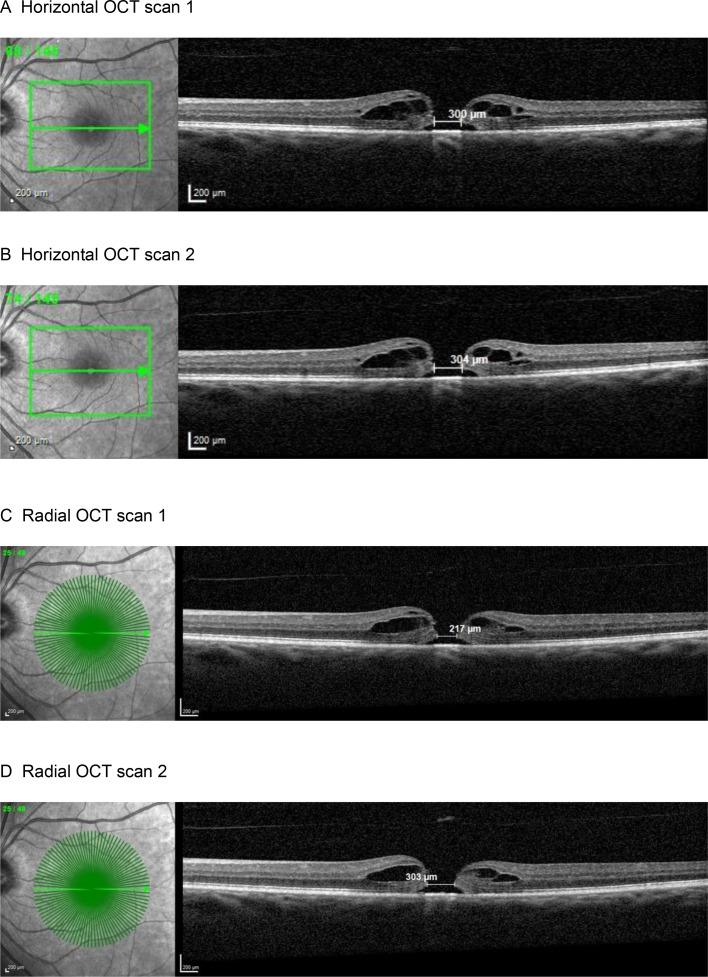

Objective: To assess the interchangeability of minimum linear diameter (MLD) macular hole (MH) size measurements in high-density horizontal and radial scan modes in optical coherence tomography (OCT).

Methods and analysis: 60 patients with a MH had repeat high-density OCT volume scans in a horizontal (30 µm interscan-spacing) and a radial (angular 3.75° interscan-spacing) mode, and the MLD was measured by five raters.

Results: There were no significant differences in the MLD measurements within the horizontal and the radial modes across repeat measurements of each rater in volume scan 1 (all p≥0.14 and p≥0.28, respectively), between volume scans 1 and 2 (all p≥0.14 and p≥0.69), among the raters (p=0.70 and p=0.60), and using all MLD measurements obtained in this study between primary and repeat measurements in volume scan 1 (p=0.10 and p=0.74) and between measurements obtained in volume scan 1 and 2 (p=0.21 and p=0.90).There was a statistically significant difference of -10.05 µm between the mean MLD of all measurements in the horizontal (n=900) and in the radial (n=900) mode (427.91 (±187.01) vs 437.97 (±184.93) µm; p<0.001). However, the variability of these differences around the mean MLD was large (95% limits of agreement -77.31 to 57.21 µm). The mean difference between all horizontal and all radial MLD measurements in a MH was for MHs that had their widest MLD within 15° of the horizontal, vertical and diagonal meridians 0.77 (±13.88) µm, -34.43 (±55.22) µm and -10.39 (± 34.62) µm, respectively.

Conclusions: Horizontal scans systematically underestimate the maximum MLD if located vertically or diagonally; however, they have less intra-rater and inter-rater and inter-scan variability in MLD measurements as compared with radial scans. Therefore, the two scan modes are not interchangeable but rather complement each other. These results may be limited to the MLD range analysed (125-924 µm).